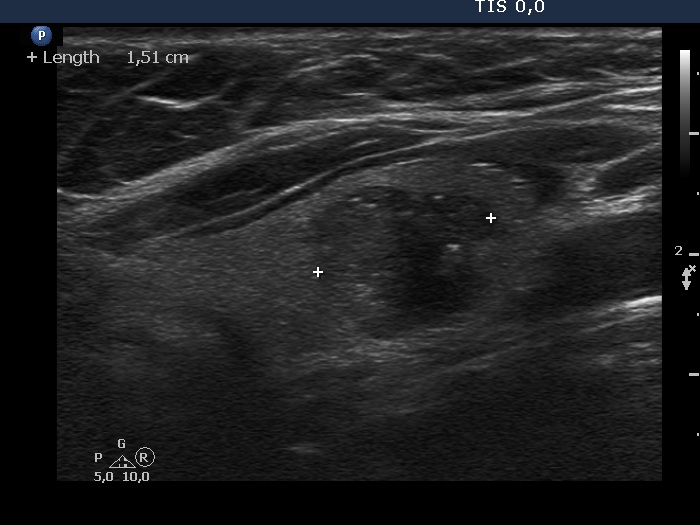

Ultrasonography. The thyroid was echonormal. There was a hypoechoic lesion in the left lobe. It was equivocal whether the lesion was composed of multiple nodules, therefore most of the lobulations seen on the surface of the mass were of questionable origin. However, there were protrusions in the ventral and medial part of the mass which were suspicious being pathological lobulations.